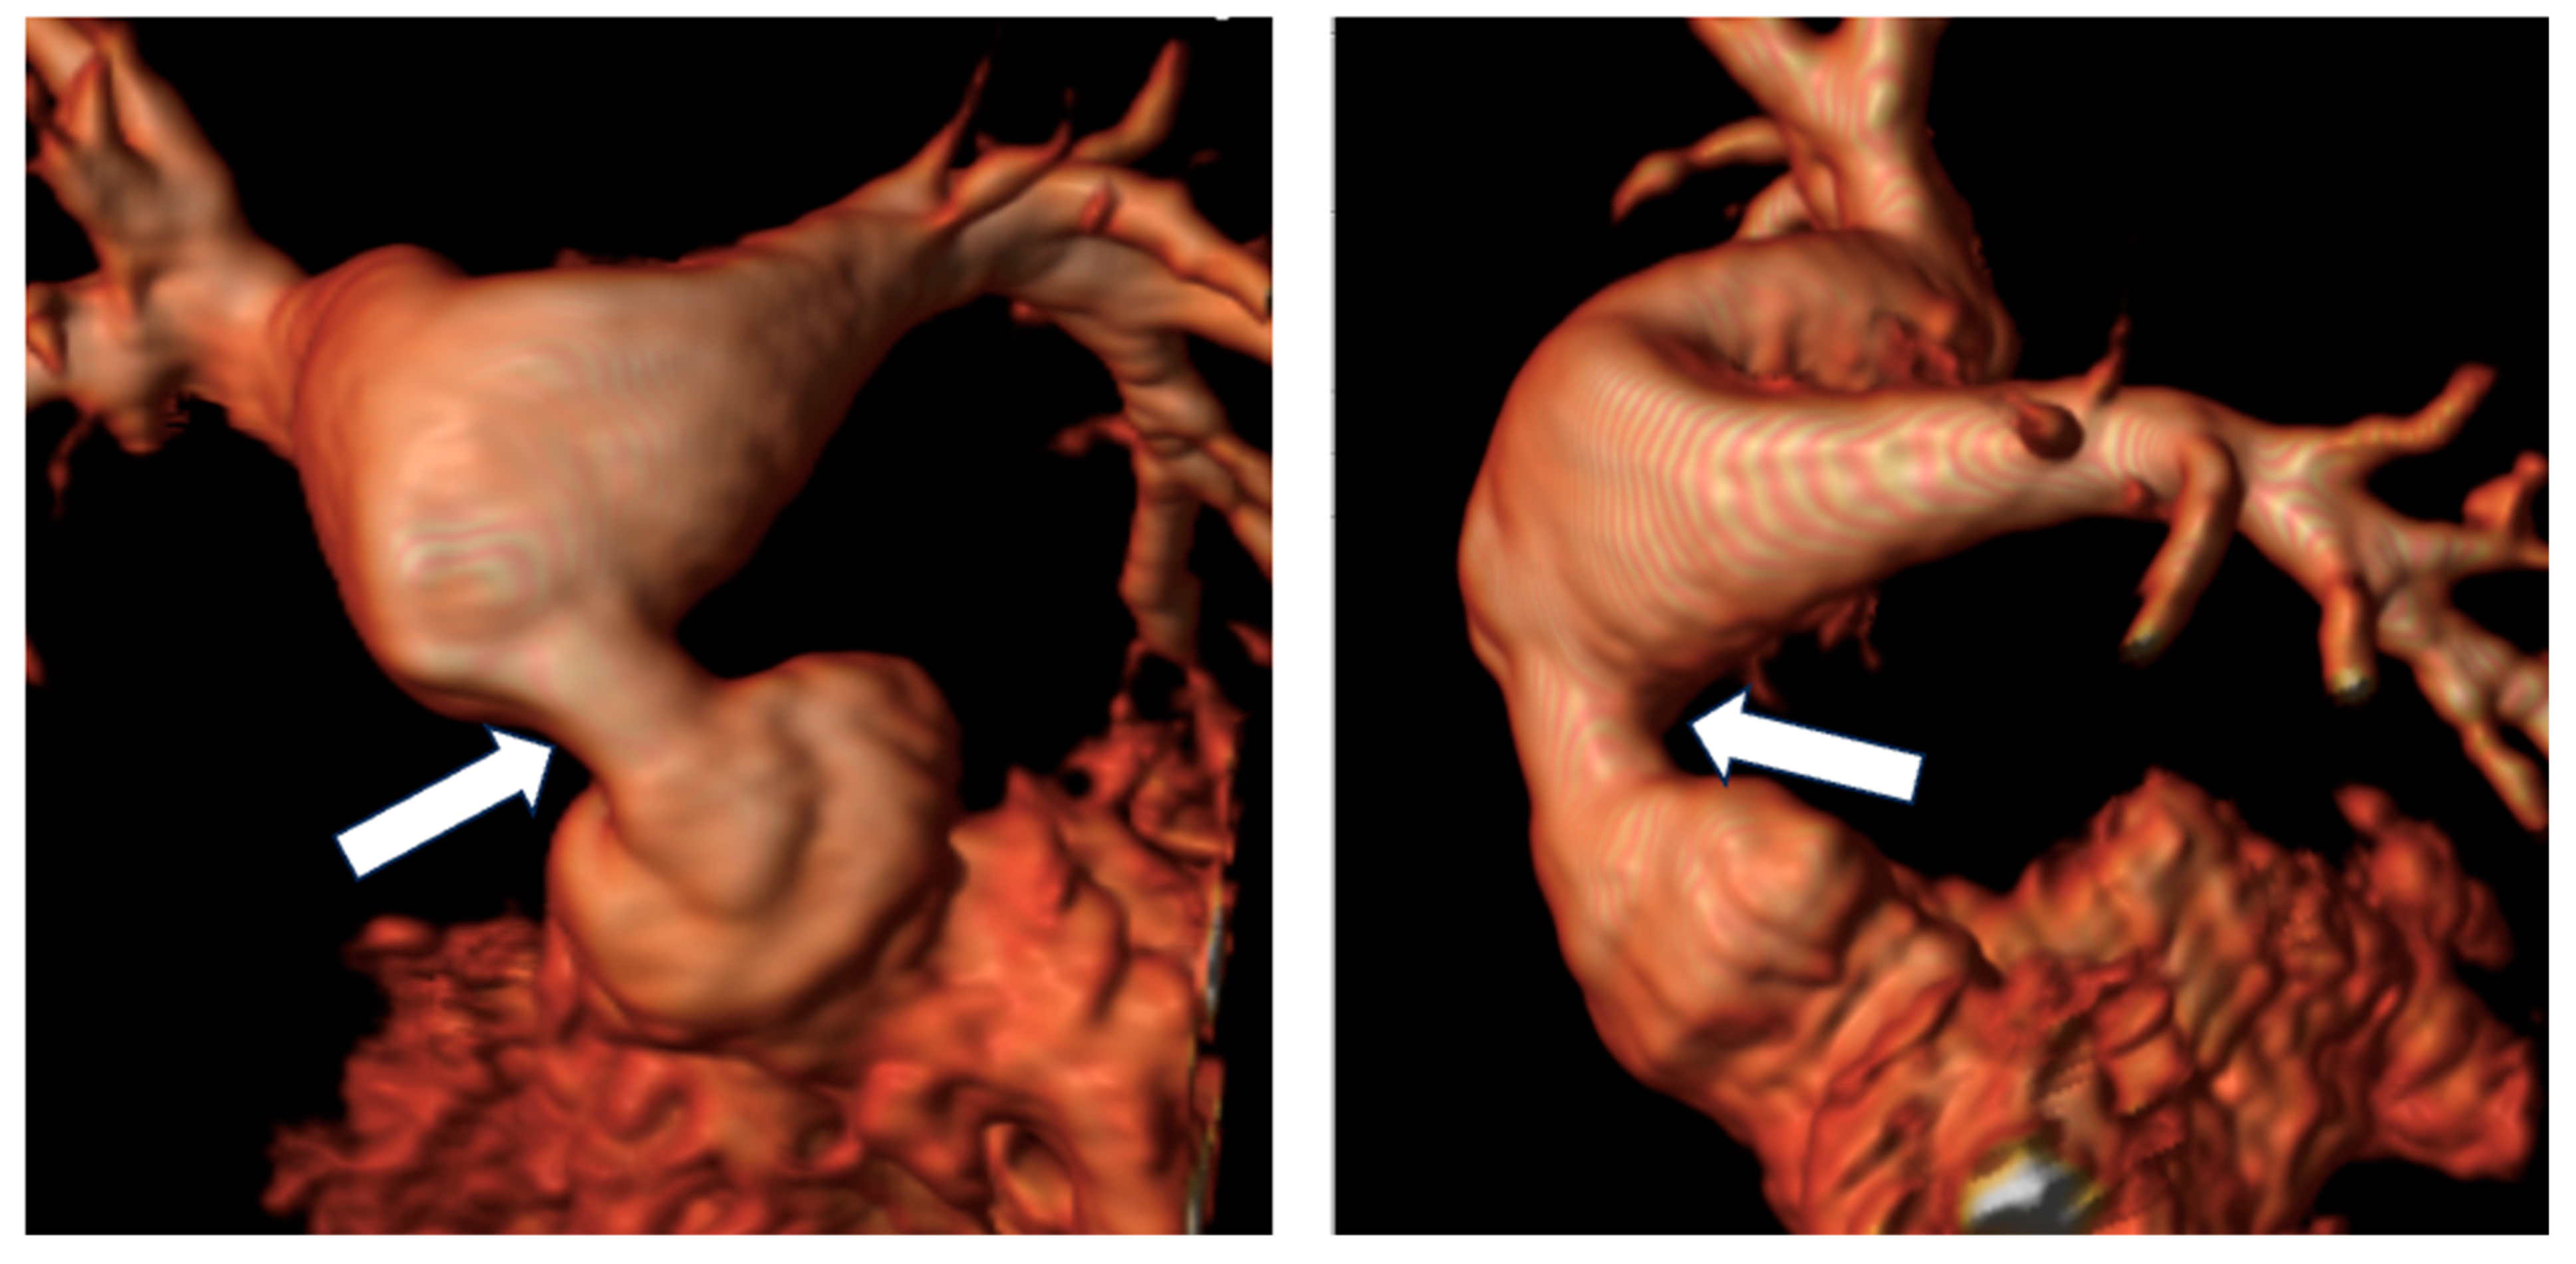

2.3. Coarctation of the Aorta